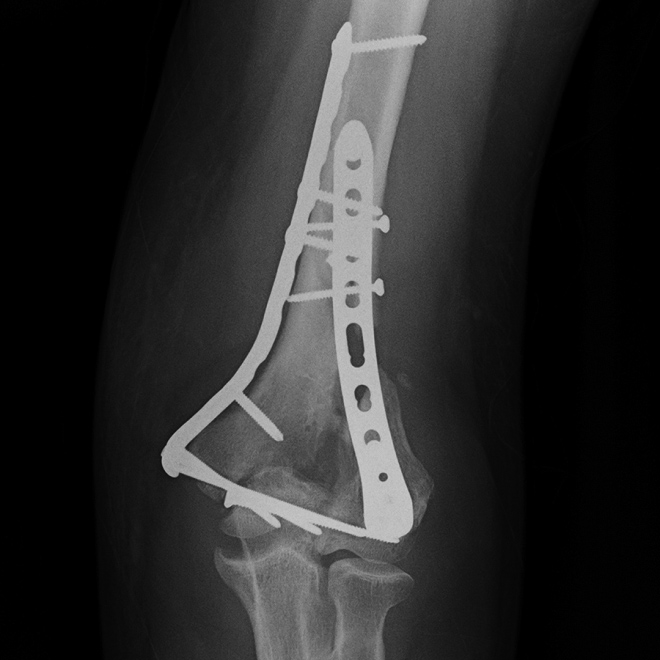

While periprosthetic fractures may occur acutely or chronically following fracture fixation or arthroplasty, CT may be more beneficial in the chronic setting to accurately assess the exact extension of the fracture and residual bone volume, which may be obscured by overlying surgical hardware (Figure 8) (Ohashi, 2009). Further, CT may be helpful to better assess multiple overlapping screws or complex hardware before surgical intervention. Cross-sectional imaging with CT or MRI may also be useful for the assessment of incomplete or stress fractures resulting in chronic post-operative pain.

Fracture healing and joint fusion may be assessed readily with radiographs, but the presence of callus formation alone does not predict progression to complete healing, and the presence of osseous bridging is considered a more reliable indicator of union (Figure 9) (Ohashi, 2009). CT has been found to be more accurate for the determination of osseous bridging, as radiographs may either underestimate or overestimate the extent of bone fusion (Krestan, 2006; Grigoryan, 2003). The presence of exuberant callus formation may obscure the evaluation for osseous bridging on radiographs, and multiplanar CT allows direct visualization of the fracture site. In addition, fine central osseous bridging at the site of small fractures and bone grafts, such as in treated, non-united scaphoid fractures, is better assessed with thin slice CT images (Figure 10). Finally, some articulations are difficult to assess due to overlapping anatomy, such as the posterior subtalar and Lisfranc joints, and CT offers superior delineation of the joint spaces following arthrodesis.

Radiographs remain the gold standard for assessing the integrity of implanted hardware; however, CT may be useful in particular cases. Prior to complete fracture union, hardware failure poses a significant impediment to fracture healing, and, in fact, may be an indicator of fracture non-union as chronic mechanical stress at the persistent fracture site results in hardware fracture. Consequently, CT examinations for fracture healing should also include a close inspection of surgical hardware, particularly in cases of non-union.